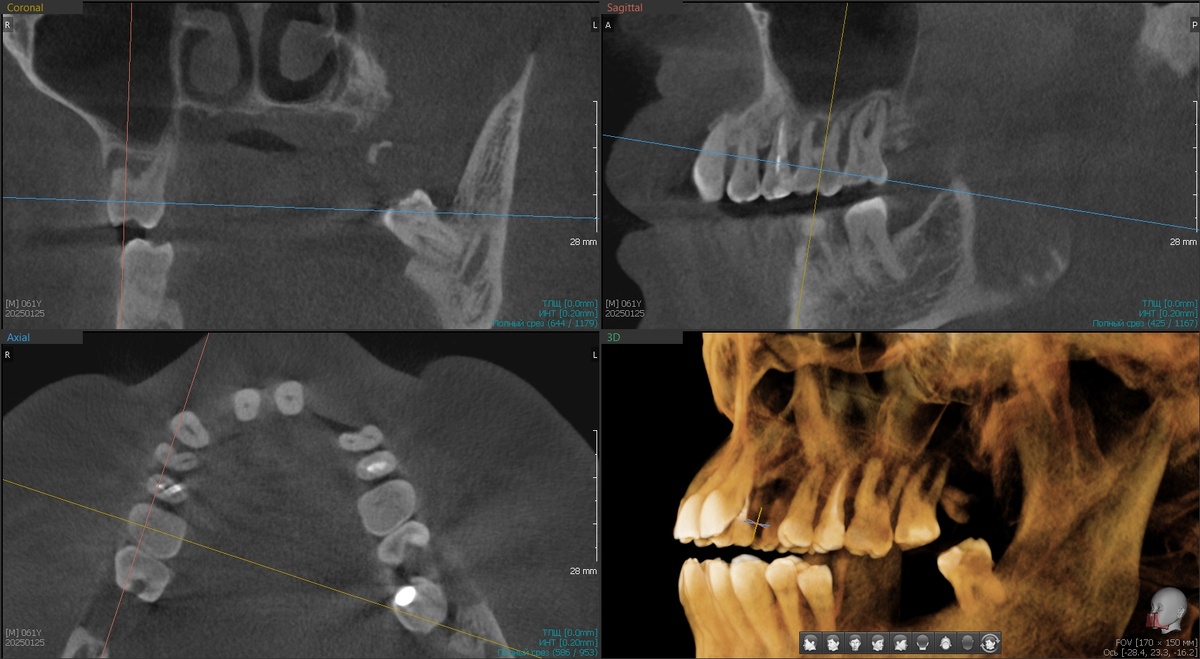

Запрос на верхнюю челюсть. На первый взгляд многим покажется, что спасти своё можно, так думала и я, пока не открыла снимок КТ и не оценила состояние кости.

Хронический генерализованный пародонтит тяжёлой степени тяжести - вон оно что, так это называется. Кость никогда уже не вырастит, зубы обречены. Хорошие зубы и плохая кость - печальное сочетание.

Можно ли оставить такие зубы? Можно, но инфекция в зоне фуркаций корней будет находиться всегда, потому что пациент не способен будет дома очистить всё вот это вот, очень уж сложный рельеф. Не будет очищения - пародонтит будет продолжать уничтожать кость. А, значит, для классической имплантации может не остаться условий.